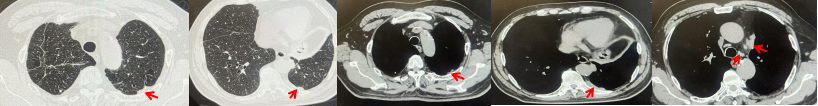

2024.11.19患者出现右侧胸痛,复查胸部CT检查示右侧胸膜肿物,大小约31mmX24mm,右侧4、5肋骨骨质破坏,考虑转移(如图2)。建议患者穿刺活检取病理明确诊断,患者拒绝,经MDT会诊后结合影像学表现及病史考虑为胸膜转移,肋骨转移,分期为rT0N0M1a IVA期,DFS仅仅17个月。2024.12.05起行信迪利单抗联合培美曲塞+卡铂方案治疗4周期,复查胸CT评效PR(如图3)。之后给予信迪利单抗+培美曲塞维持治疗6周期,期间复查CT评效PR(如图3)。目前信迪利单抗+培美曲塞维持治疗中,截止至目前PFS约为8个月,治疗期间未出现明显毒副反应。

图2:患者胸膜及肋骨转移(2024.11)胸部CT肺窗、纵隔窗及骨窗

图3:患者免疫联合化疗治疗后胸部CT,(A、B)图展示信迪利单抗联合培美曲塞+卡铂治疗

4周期(2025.02)疗效,(C、D)图展示信迪利单抗+培美曲塞维持治疗6周期(2025.07)疗效